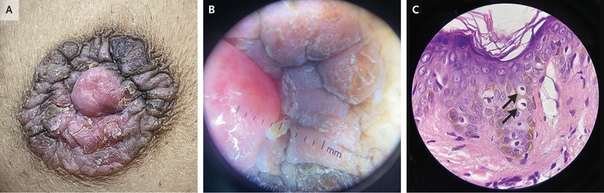

Жалобы на заложенность в ушах. Ранее у пациентки была выявлена ретркация барабанной перепонки, рекомендовано выполнять пользу Вальсальвы, что временно уменьшало ощущение заложенности.

В течение 6 лет пациентка выполняла упражнение 4 раза в день ежедневно.

При осмотре: в толще барабанных перепонок пузырьки воздуха, признаков отека или воспаления нет. Аудиография: умеренная кондуктивная тугоухость справа, нормальный слух слева.

Вероятнее всего изменения барабанных перепонок вызваны за счет частого выполнения пробы Вальсальвы.

Рекомендовано снизить интенсивность и частоту выполнения пробы.

При осмотре спустя 1 месяц отмечено улучшение.

Masafumi Ohki. Hyperectasis of the Tympanic Membrane. N Engl J Med 2013; 369:1046. DOI: 10.1056/NEJMicm1213263